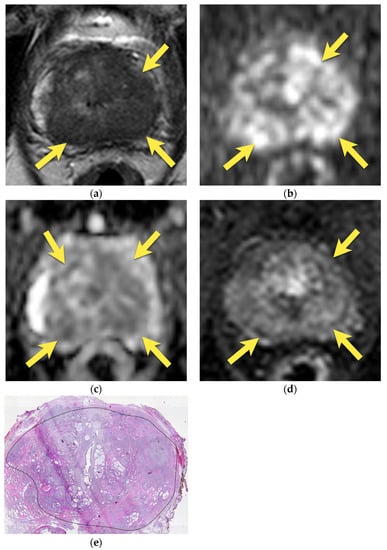

10. Prostatic Abscess